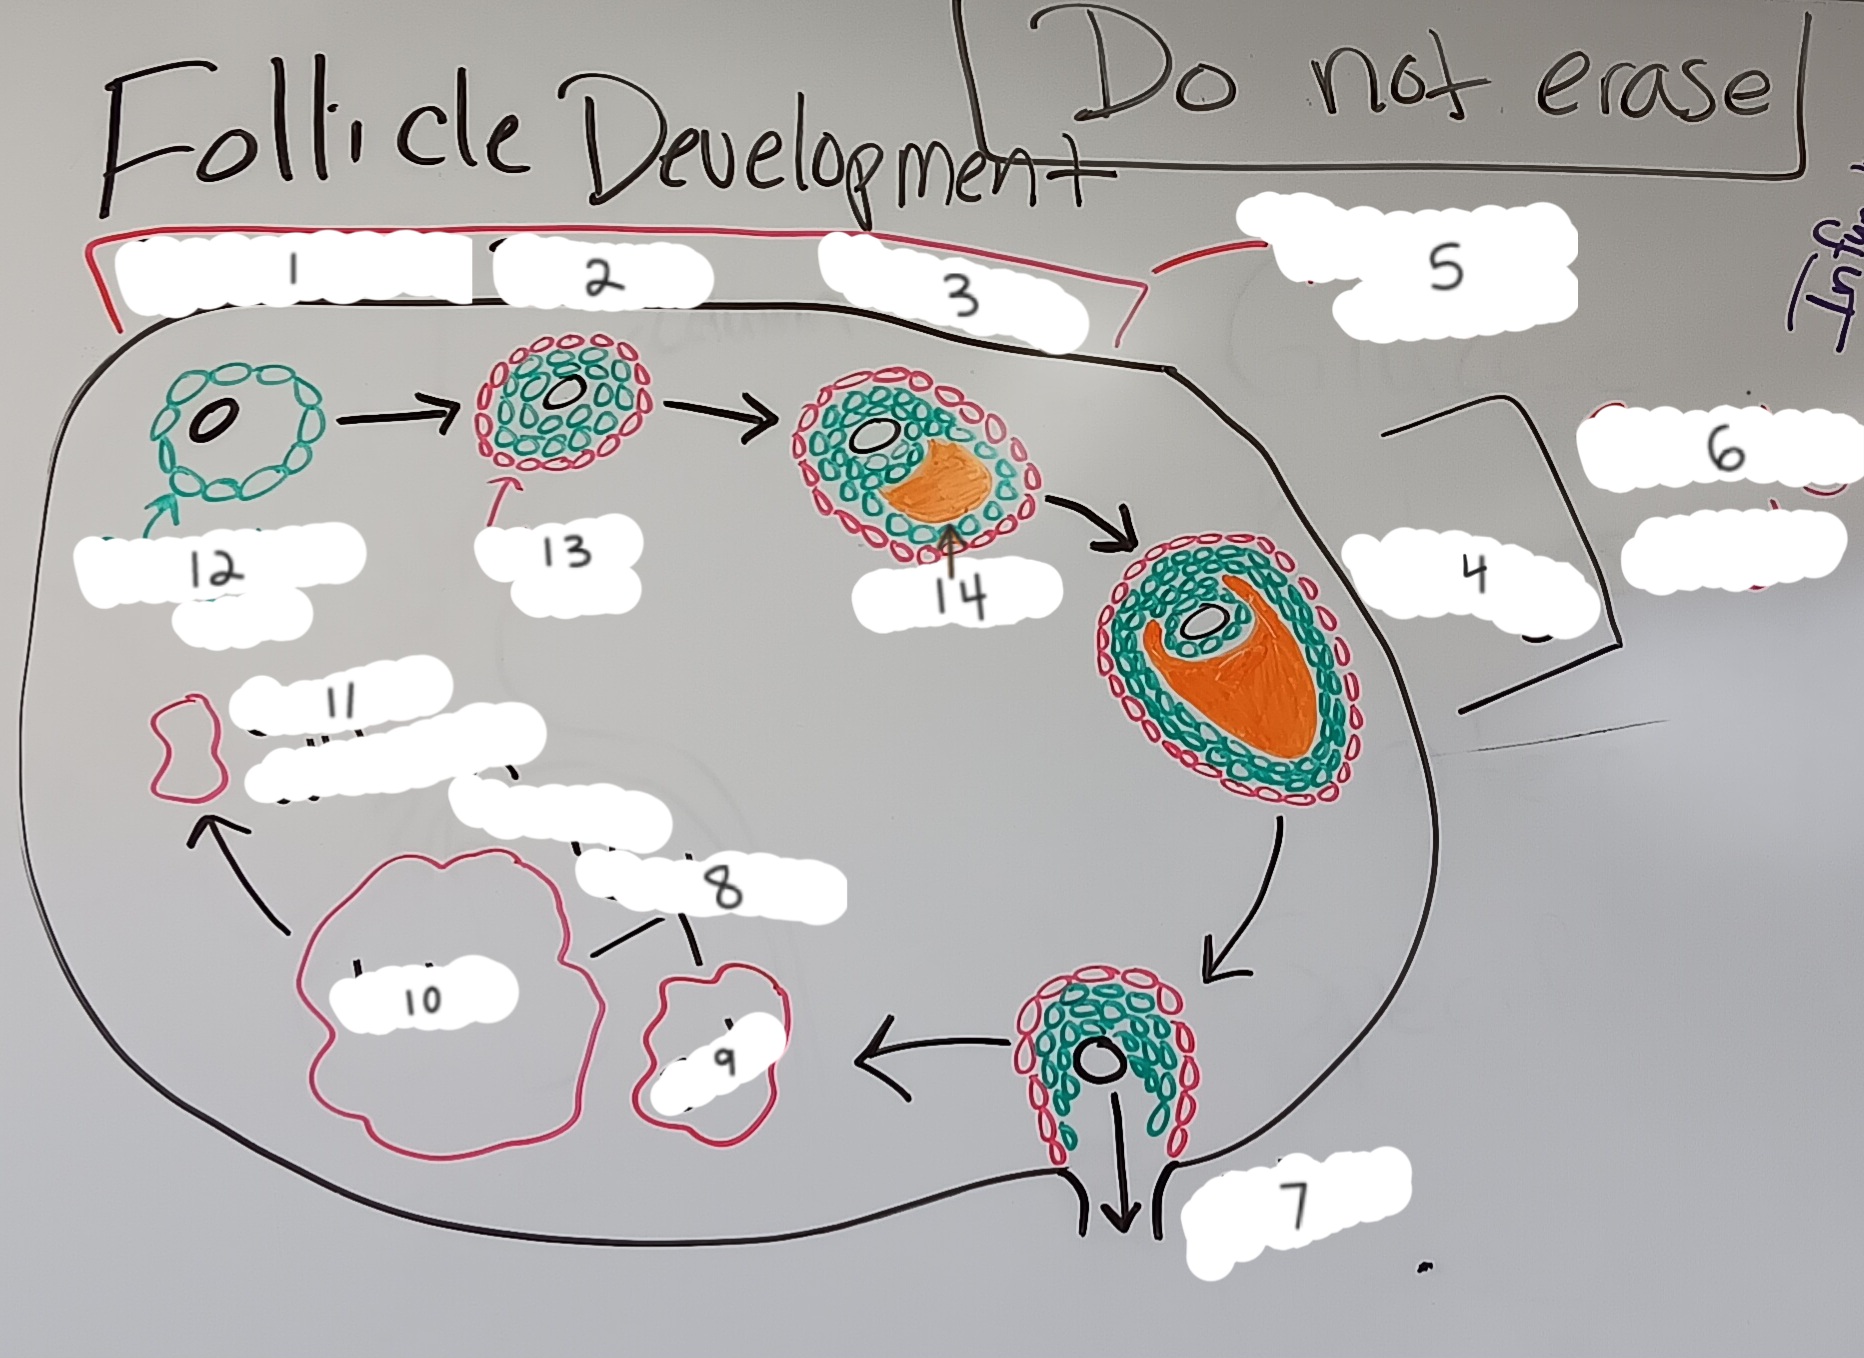

Primordial follicle

1

Primordial follicle

Primordial follicle

1

Primary follicle

2

Primary follicle

Primary follicle

2

Secondary follicle

3

Secondary follicle

Secondary follicle

3

Tertiary follicle

4

Tertiary follicle

4

Mature follicle

5

Mature follicle

Mature follicle

7

Antrum

10

Zona pellucida

9

Theca folliculi

8

Corona radiata

Corpus luteum

Corpus luteum

Corpus albicans

Corpus albicans

corpus luteum

8

early corpus luteum

9

late corpus luteum

10

corpus albicans

11

granulosa cells

12

theca cells

13

antrum

14